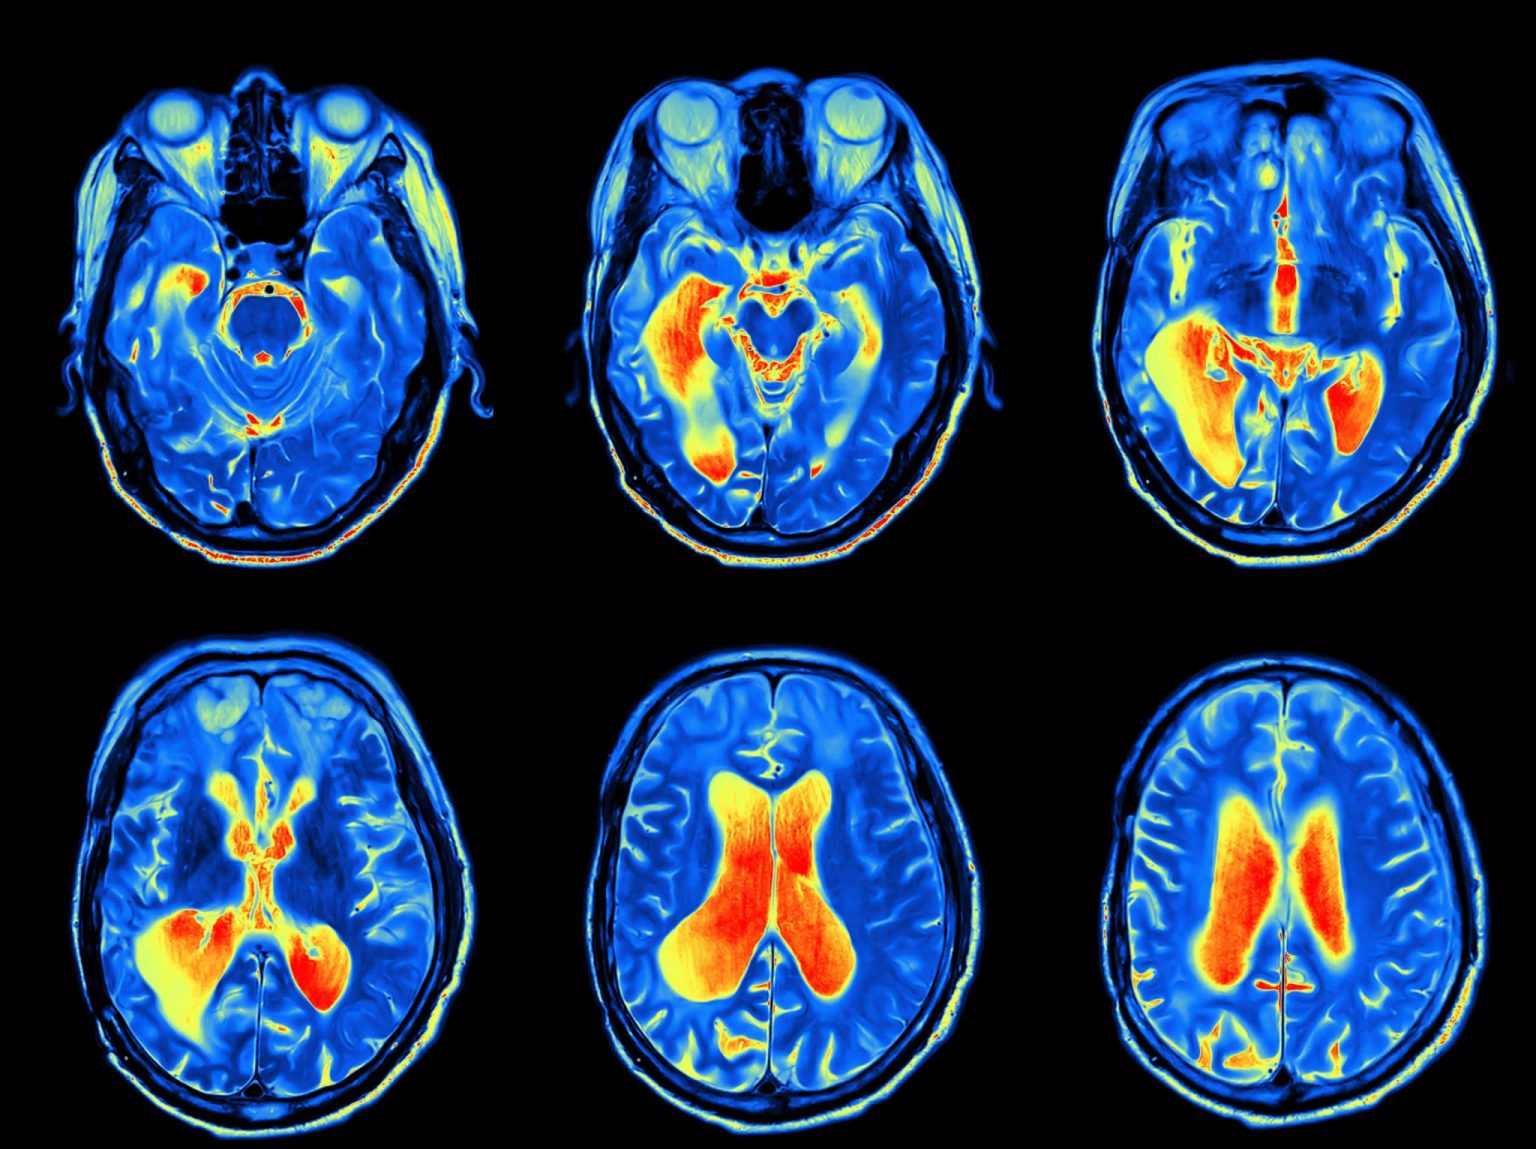

In order to diagnose tumors of the skull base, the physician will rely on a physical exam, a neurological exam and imaging studies. These might include CT scan, MRI, bone scan and positron emission tomography (PET) scan.